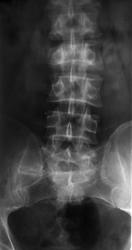

Мужчина с 1971 года рождения, очень давно попал в ДТП... Что с крестцом, неоартроз?

Рентгенограмму делали на поясничный отдел, так как задача стояла в исключении перелома L3, изменения в крестце случайная находка.

А "сплюснут" Л2....?

Компрессионный перелом L3....нет, всё ж L2

Компрессионная деформация L2, перелом боковой массы крестца справа с исходом в неоартроз.

Как-то нет убежденности, что это "второй" позвонок.

Вы правы, ребер для полного удовлетворения не хватает...

У меня получился третий.

Переходный позвонок с признаками люмбализации (наличие диска между ним и нижележащим крестцовым позвонком, а также свободный левый поперечный отросток), и сакрализации (сильно гипертрофированный правый поперечный отросток с формированием неоартроза между ним и крестцом).

И еще: Вопросик о счете поясничных позвонков. откуда их считать? Сверху? Снизу?. если сверху то как оценивать Тh12 без последней пары ребер? (Думаю что делать снимки грудного отдела просто для подсчета - незачем) Кстати, в данном случае, вверху снимка в прямой проекции виден позвонок без ребер - возможно что он будет L1, тогда поясничных позвонков 6.

Люмбализация 1 крестцового позвонка, соответственно- компрессионный перелом 3 поясничного позвонка.

Говорил уже много раз, повторюсь, пожалуй - переходный, ассиметричный, неподвижный, с образованием неоартроза справа, пояснично-крестцовый позвонок (это для данного конкретного случая).

Чтобы "не впутывать сюда ни "люмбализацию", ни "сакрализацию", так что "третий", Андрей Юрьевич сразу об этом намекнул, а потом и сказал)))